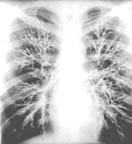

黃桿菌肺炎體徵

黃桿菌肺炎.腦膜膿毒黃桿菌本屬中公認的致病菌。菽氏統計該菌引起的77例化膿性腦膜炎,新生兒占96.1%,兒童占1.3%,成人占2.6%。成人病例多見於年老體弱者。陳氏報告1例肺炎,患者入院痰培養為變形桿菌,左肺尖外大片高密度影。曾給紅黴素及頭孢哌酮,一度好轉,入院第3周發熱又起,左心緣房胸片顯示大片模糊影,左下肺底積液及外下包裹積液。痰培養3次該菌(FM)。除對羧苄西林、四環素中度敏感外,對其他多種青黴素、頭孢菌素、氨基甙類、氯黴素及磺胺甲噁唑等均耐藥。患者因昏迷,給人工機械通氣,用四環素及青黴素病情好轉。但氣管插管脫出,又發生消化道出血,因吸入窒息而死。晏氏也曾報告1例患結節性彈力纖維變性伴黑頭綜合徵,胸片為雙下肺炎,疑雙側胸腔積液。抽取胸水620ml,為滲出液,後變為血性。入院1周痰培養為此菌,5天后變為純培養,兩天后死亡。據Olsen檢查男女泌尿生殖器的27600例體檢中,檢出114例腦膜敗血性黃桿菌,其中來自女性者有100株。因此他認為女性生殖器可能成為該菌在醫院的感染源,應引起足夠的重視。同時他還在醫院不同部位採集269份標本進行培養,其中33份陽性,在住院病人及醫務人員中,也發現有呼吸道帶菌者,甚至有報導,在消毒器械用的1‰氯己定浸液中也發現有此菌。